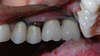

POSE DE COURONNES CERAMIQUES